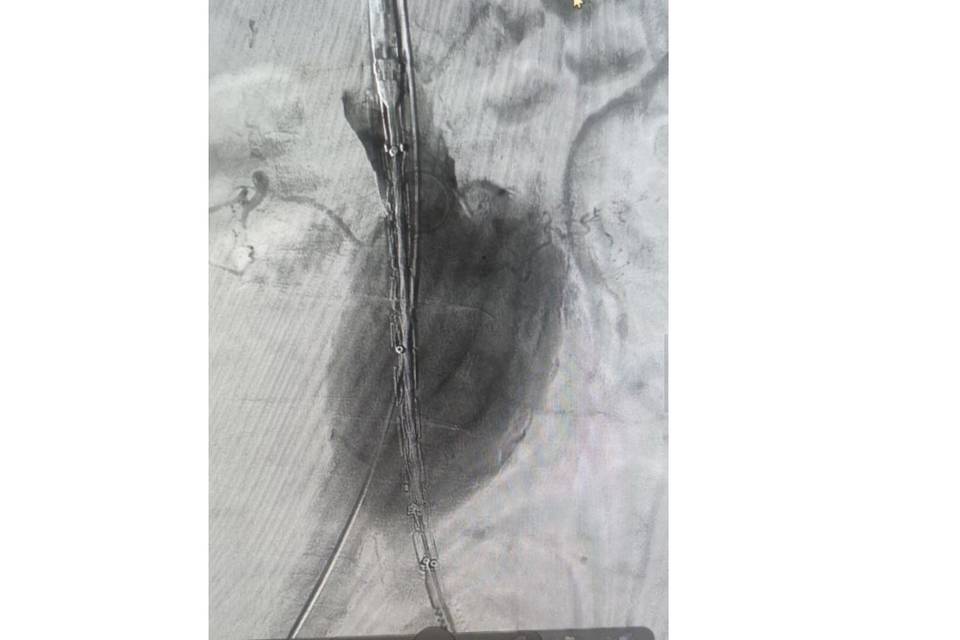

Пациенту укрепили стенку аорты с помощью стент-графта.

Как сообщает комитет здравоохранения Волгоградской области, в областной клинической больнице №1 успешно провели сложную операцию по установке стент-графта для лечения аневризмы брюшной аорты. Это вмешательство показывает высокий уровень сосудистой хирургии в регионе.

Стент-графт состоит из стента – металлической или полимерной сетки, которая поддерживает стенку сосуда, и графта – тканевой или синтетической оболочки, обеспечивающей дополнительную защиту и прочность. Конструкция укрепляет стенку аорты изнутри и создает новый канал для кровотока. Это помогает восстановить функцию магистрального сосуда и предотвратить опасные осложнения.